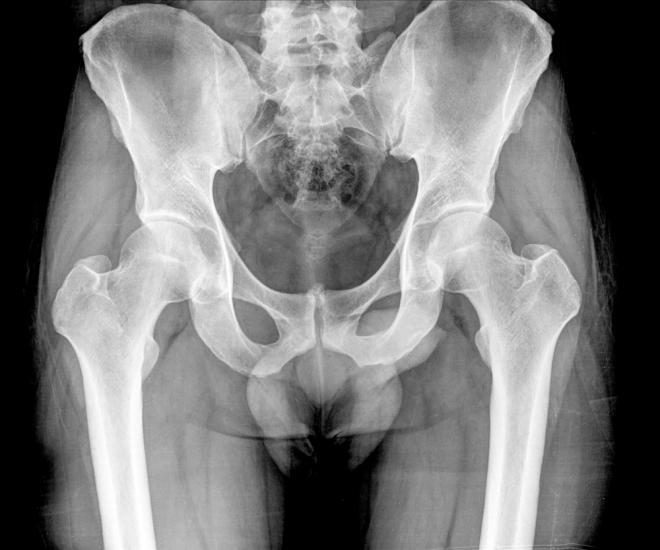

На рентгенограмме 92-летней женщины врачи обнаружили беременность, замершую 50 лет назад

В Чили в брюшной полости у женщины выявили пятидесятилетний зародыш. 92-летняя женщина после падения обратилась в госпиталь, где ей сделали рентген. На снимке врачи увидели, что у неё внутри имеется двухкилограммовый мумифицированный зародыш, погибший, вероятно, на сроке 7 месяцев.

Этот редкий феномен, известный как литопедион (по-гречески «окаменелый ребёнок»), возникает, когда плод погибает во время беременности и кальцифицируется вне матки – это позволяет ему остаться внутри тела. Принимая во внимание возраст пациентки, доктора решили не оперировать её и выписали через несколько часов.

Во всей истории мировой медицины известно лишь около 400 случаев литопедиона.